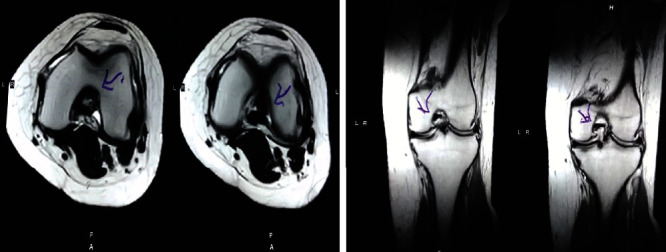

治療后一個月進行隨訪。在第一次細(xì)胞治療后,患者的疼痛明顯減輕。第二次療程后,她沒有疼痛,并注意到運動范圍有所改善。持續(xù)的物理治療也觀察到下肢肌肉力量的增加。從治療開始(11個月前)到最后一次隨訪(4個月前),患者按照建議的飲食和基于運動的方案減重了11公斤。因此,她現(xiàn)在整體身體健康,能夠更舒適地進行日常生活活動。表3顯示治療前后的MRI檢查結(jié)果。人物的圖1和的和圖2顯示半月板撕裂的治療前和治療后(1年后)圖片。觀察到損傷程度的改善圖2。